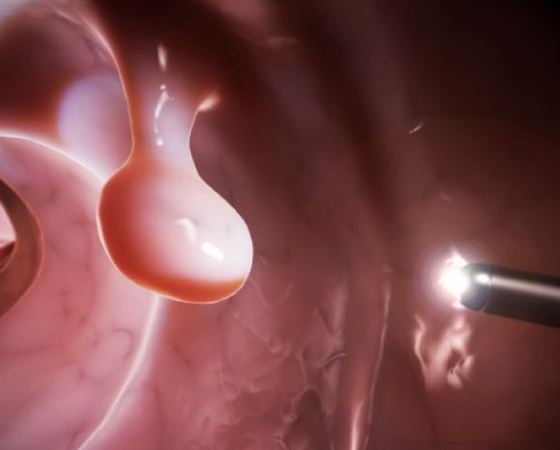

Ο καρκίνος του παχέος εντέρου ξεκινά συχνά ως πολύποδας -καλοήθης όγκος στην εσωτερική επιφάνεια του παχέος εντέρου. Οι δύο πιο κοινοί τύποι πολύποδα του εντέρου είναι τα αδενώματα και οι υπερπλαστικοί πολύποδες. Αναπτύσσονται όταν υπάρχουν λάθη στον τρόπο που τα κύτταρα αναπτύσσονται και επιδιορθώνονται στο εσωτερικό του παχέος εντέρου. Οι περισσότεροι πολύποδες παραμένουν καλοήθεις, αλλά μερικοί έχουν τη δυνατότητα να μετατραπούν σε καρκινικούς. Η αφαίρεσή τους αποτρέπει τον πρόωρο καρκίνο του εντέρου.

Επειδή ο καρκίνος του παχέος εντέρου είναι κρυφός, οι απεικονίσεις είναι το κλειδί για την έγκαιρη διάγνωση. Ξεκινώντας από την ηλικία των 50 ετών οι άνθρωποι θα πρέπει να υποβάλλονται σε κολονοσκόπηση κάθε 10 χρόνια. Αυτή η διαδικασία χρησιμοποιεί μια μικροσκοπική κάμερα για να εξετάσει το σύνολο του παχέος εντέρου και του ορθού. Οι εξετάσεις αυτές δεν πρέπει να γίνονται μόνο για να βρεθούν νωρίς τυχόν όγκοι, αλλά και για να αποτραπεί ο καρκίνος του παχέος εντέρου με την αφαίρεση πολυπόδων.